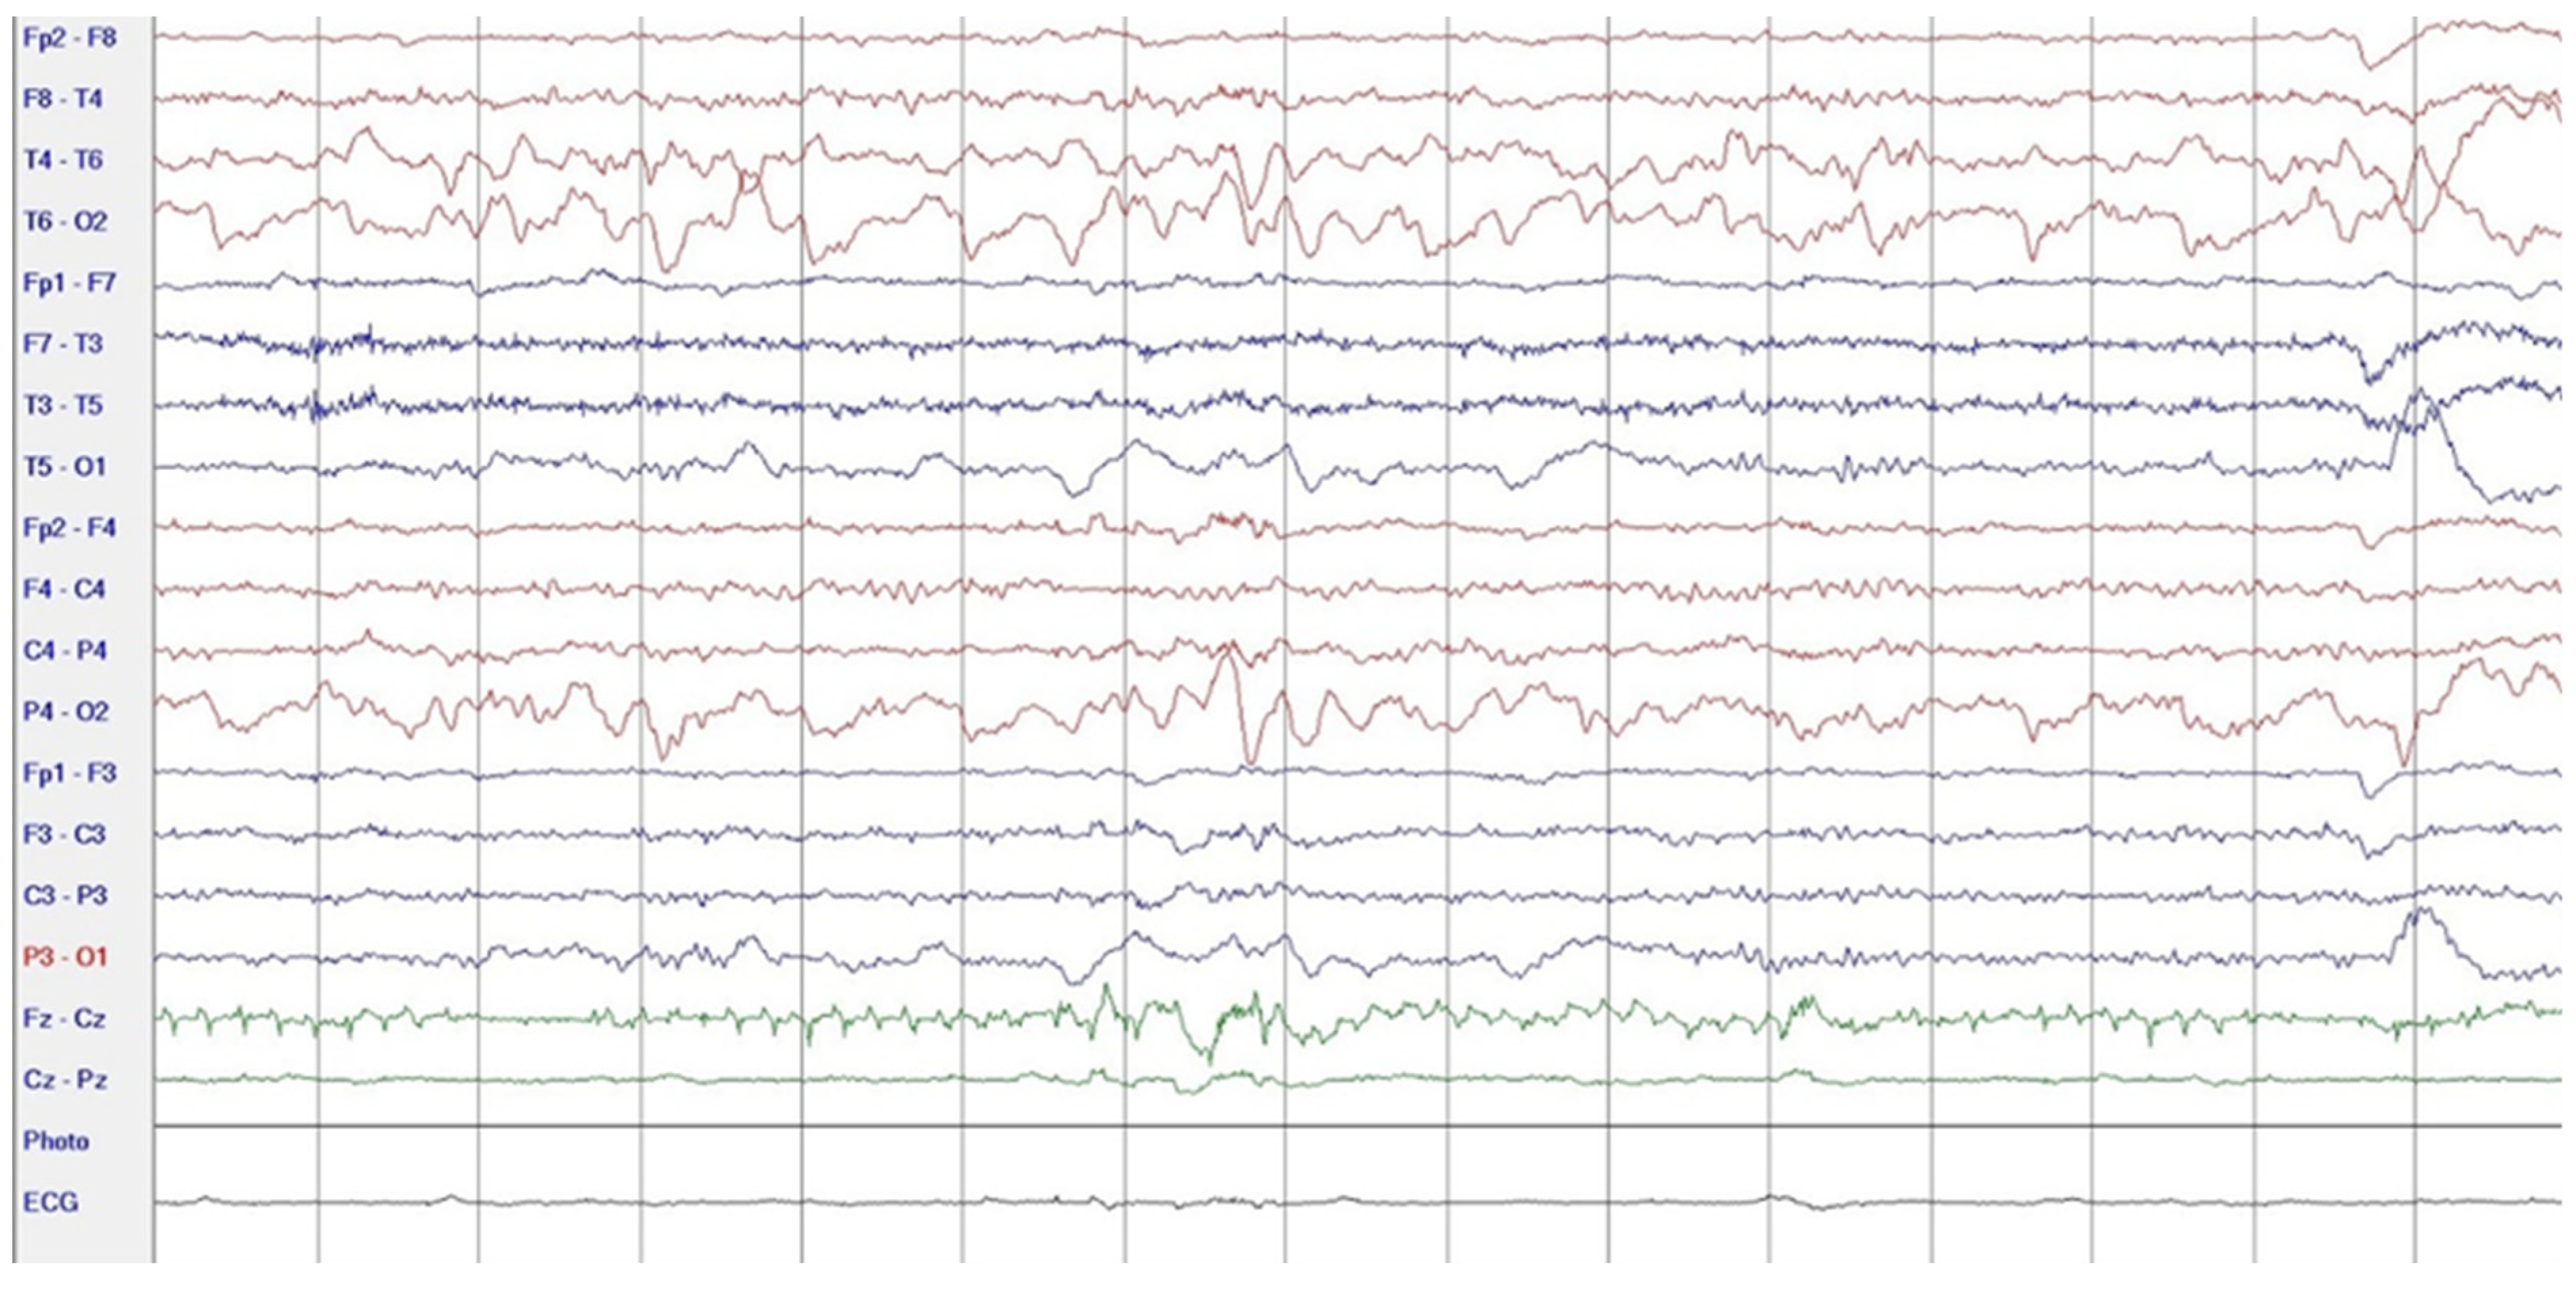

During hospitalization in the neurology ward, Holter EEG was performed in which seizure episodes corresponded to changes in the recording. Interictal EEG showed rapid activity followed by slow theta waves and several sharp and slow wave complexes (Figure 1 and Figure 2). Topiramate was added to valproic acid at a target dose of 2 mg/kg of body weight. Gradual seizure relief was observed in the following weeks, and there were no other neurological manifestations for another nine months. After that time, in December 2021, the patient was admitted to the pediatric ward due to impaired consciousness and persistent vomiting, followed by paresis of the lower limbs. A brain MRI was performed, which showed “T2/FLAIR images reveal poorly defined areas of increased signal in the brain’s white matter, both above and below the tentorium, as well as in the periventricular and subcortical regions. These areas correspond to low signal regions in T1 images. The largest change area measures 19 × 14 mm and is located in the right middle cerebellar peduncle, which merges with changes observed in the pons. Additionally, there is a lesion in the right thalamus, measuring 10 × 24 mm, along with numerous scattered foci in the corona radiata and between the basal nuclei. Overall, the imaging findings primarily suggest acute disseminated encephalomyelitis (ADEM)” (Figure 3 and Figure 4). Cerebrospinal fluid examination revealed oligoclonal bands and an elevated protein level of 118.5 mg/dL (reference range: 15.0–45.0 mg/dL) and a slightly elevated leukocyte level of 29/mm3 (lymphocytes 72.4%, neutrophils 27.6%).

Figure 1.

EEG trace: rapid intraictal rate (December 2020).